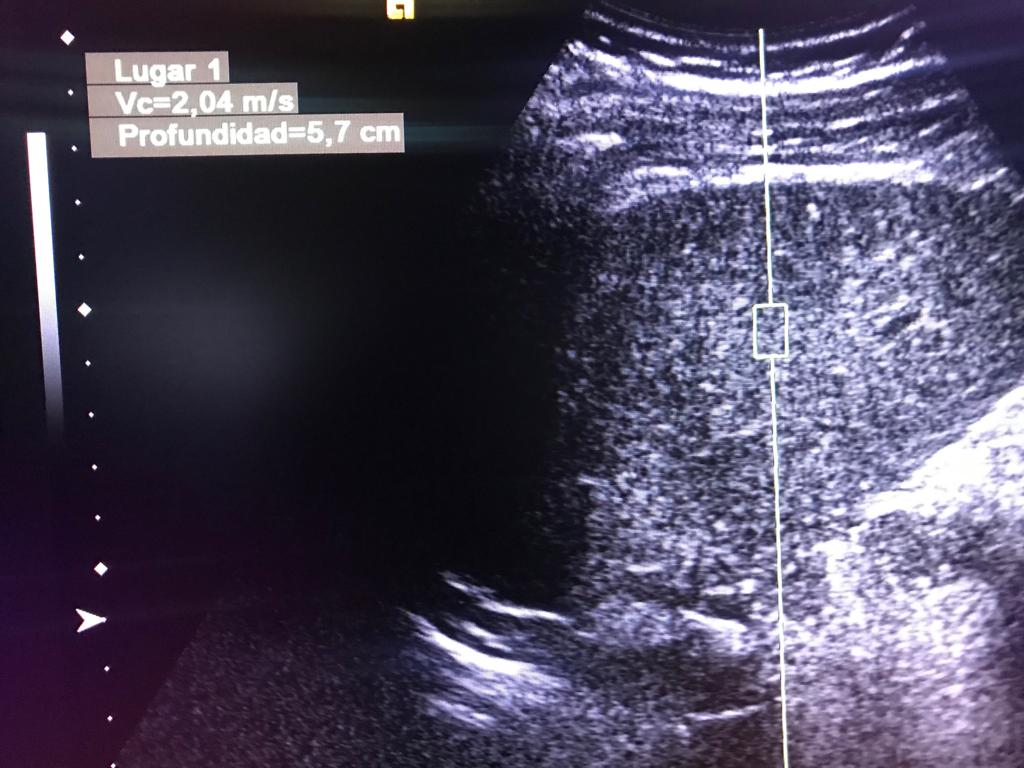

Masculino de 52 años, con cirrosis hepática. La elastografía ecográfica evidencia fibrosis Categoría F3 según escala de METAVIR y la presencia de múltiples nodulaciones, que en su mayoría son menores a 2 cm.